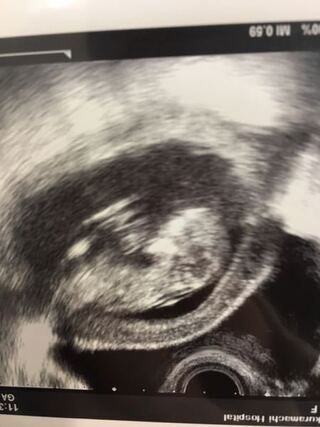

妊娠12週0日の超音波検査 ベドリントンテリア レックスの成長日記と私の初妊娠ライフin Perth

胎児の首の後ろのむくみ 浮腫 Nt とは 妊娠初期 All About

妊娠12週前後 赤ちゃんの首の後ろの浮腫 Nt と胎児ドック しのくろ育児録

胎児の首のむくみ Nt クリフム夫律子マタニティクリニック